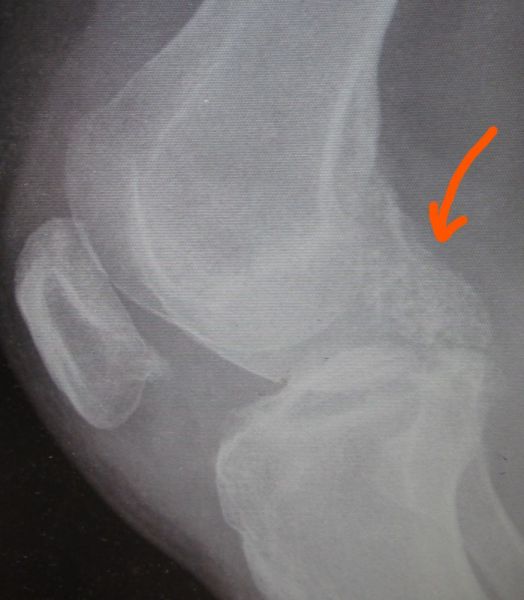

1. Popliteal extraskeletal chondroma of the right knee in a 38-year-old female.

Treatment: Surgical removal

I. Before the surgery , lateral x-ray of the knee shows the chondroma (red arrow) II. Post-surgery, lateral x-ray of the knee shows that the chondroma has been removed III. Post-surgery, the photo (posterior site of the knee) is showing the specific approach that has been used for the operation.